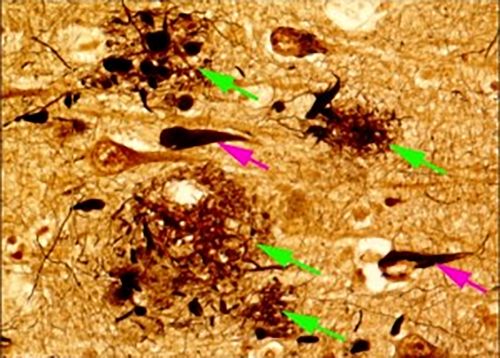

わが国でアルツハイマー病(AD)に悩む方の数は数百万人にのぼります。ADの病態メカニズムそのものを標的とする薬(疾患修飾薬)の開発が進み、脳に溜まってADの原因となるタンパク質「アミロイドβ」に対する抗体療法が実用化されました。本邦でも2023年12月より「レケンビ(一般名:レカネマブ)」が発売され、NCNP病院でも本剤を使っての治療を開始しました。この薬では、一部の患者さんに脳の浮腫(むくみ)や小出血などの副作用(ARIAと呼ばれます)が生じる可能性があり、これを予測し、安全に治療を行うことが求められています。ARIA のリスクは、APOEという遺伝子の型から推定が可能で、ε4型のAPOE遺伝子を2つ持つ場合(抗体薬の適応となる患者さんの1割程度と予測されます)に、リスクが高まることがわかっています。しかし、APOE遺伝子型の検査は現時点(※本稿初出2024年当時)ではまだ公的医療保険の適用外です。検査が保険適用となるまでの期間、患者さんの安全を確保するために、抗体薬で治療されるすべての患者さんから安全性や効能の情報を収集する「製造販売後調査」を製薬企業が行い、並行して、私たち研究者がAPOE 遺伝子検査やバイオマーカー研究を担当し、共同で患者さんの情報を登録、解析する「全国臨床レジストリ」研究を行うことになりました。

図1: アルツハイマー病治療薬のARIA発現率とAPOE遺伝子の関係

(APOE遺伝学的検査結果補足資料より引用)